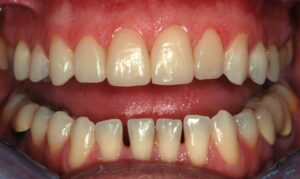

La teoria trova la sua conferma definitiva nella pratica quotidiana del nostro laboratorio. Negli ultimi mesi, abbiamo documentato numerosi casi in cui la Flow Injection Technique ha risolto sfide estetiche complesse con una naturalezza sorprendente.

Dalla chiusura dei diastemi al ripristino di intere arcate usurate, i casi trattati da Dentalstyle dimostrano che è possibile coniugare un approccio ultra-conservativo con un’estetica di altissimo livello. Vedere il paziente sorridere con sicurezza, sapendo che i suoi denti sani sono rimasti intatti, è la soddisfazione più grande per il clinico e per noi tecnici.